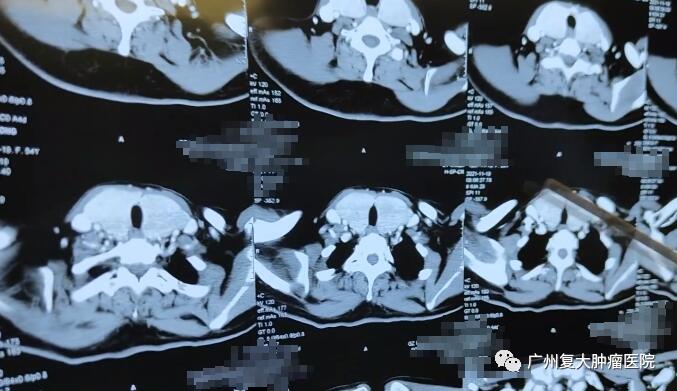

为进一步治疗,刘女士来到我院就诊。入院后完善相关检查,刘女士的双侧甲状腺III°肿大(III°即超过人体的胸锁乳突肌),其内可见多个结节状稍低密度影,较大者位于左叶,大小约10.9x0.7cm,边界模糊,增强后示明显强化。

根据患者CT检查结果,考虑患者目前甲状腺肿物明确,为明确肿瘤性质,降低肿瘤负荷,我院专家制定了甲状腺结节穿刺活检+微波消融术的治疗方案。我院牛立志院长表示,“活检能明确病理,若病理显示为良性,术中便可进行微波消融术。”